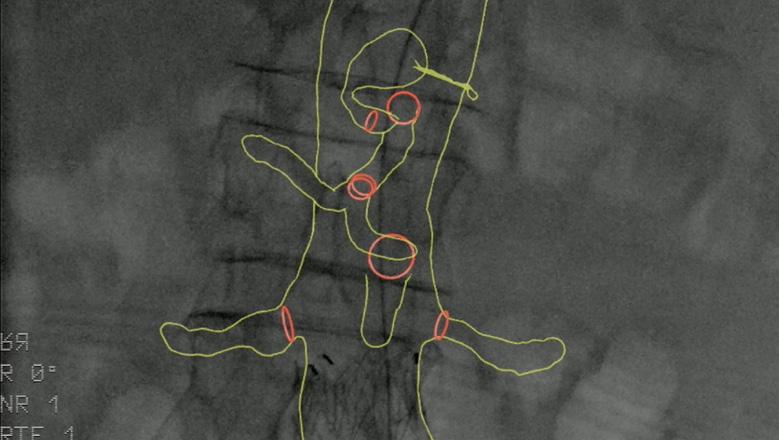

Image fusion should be considered during aortic endovascular procedures to reduce radiation exposure.1

During pre-operative planning, Cydar EV Maps processes the CT scan (even if poor quality) to accurately segment the anatomy. This, along with our detailed planning and measurement tools, provides you with the right insights and information at the right time.

Cydar EV Maps automatically adjusts the 3D overlay when changes occur due to C-arm position, patient movement or posture change, minimizing the need for additional registrations.

RECOMMENDATION 26†

Prolonged use of steep gantry angulation is not recommended during endovascular procedures.1

With Cydar EV Maps, you are able to visualize and navigate vessels, minimizing the need for steep lateral angulation and reducing radiation exposure to clinical teams and patients.

Image courtesy of Gabriel C. Inaraja